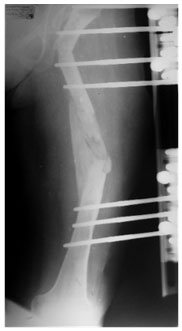

After Fixator Removal

The full length x-ray after removal is showing good correction. The tibia also has some shortening, which was addressed in the 2nd stage.